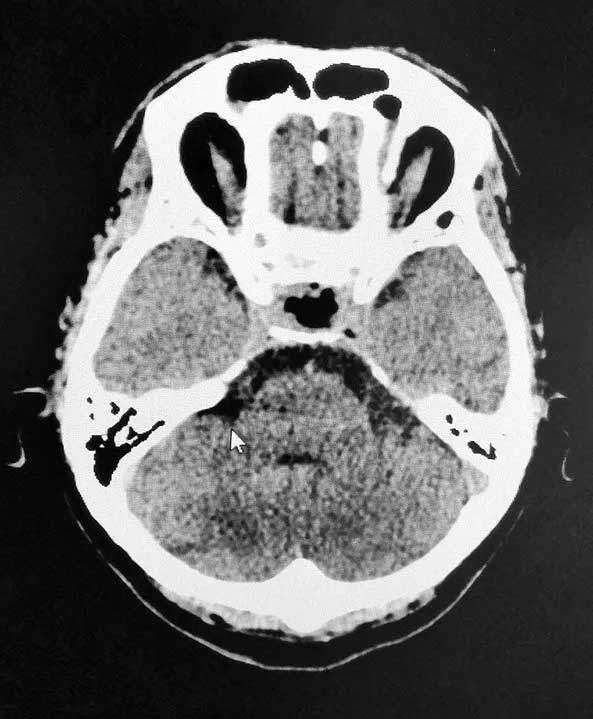

近期,上海藍十字腦科醫(yī)院6B病區(qū)收治了這樣一位典型患者。一位男性垂體瘤患者,患者一年前出現視物模糊情況,起初他以為是眼睛問題,但是到醫(yī)院眼科檢查時未查出明顯異常。來院后經檢查,患者雙側視野缺損,后經醫(yī)院MR檢查確診為3公分垂體巨大腺瘤;颊呤中g指征明確,無明顯手術禁忌,在征得家屬同意后,李士其教授在吳治群博士協助下經蝶竇入路成功為患者進行了手術,顯微鏡下將鞍內腫物切除。經過十余天恢復,目前患者已順利出院。

▲ 術后影像,腫瘤被切除